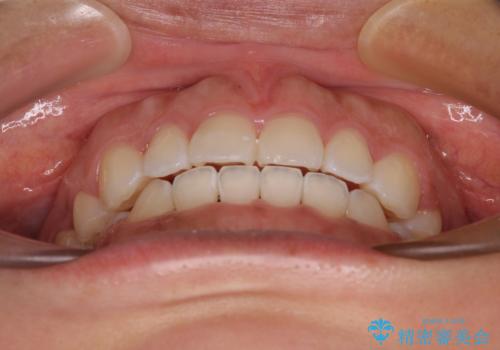

- 口が閉じにくさを気にして来院された患者様です。

上下の前歯が前方に突出していたため、上下左右の第一小臼歯4本を抜歯し、ワイヤー装置にて抜歯矯正を行うこととしました。

上下前歯部の被蓋関係を改善するの時間がかかり、3年間を要することとなりましたが、スッキリとした口元に仕上がりました。